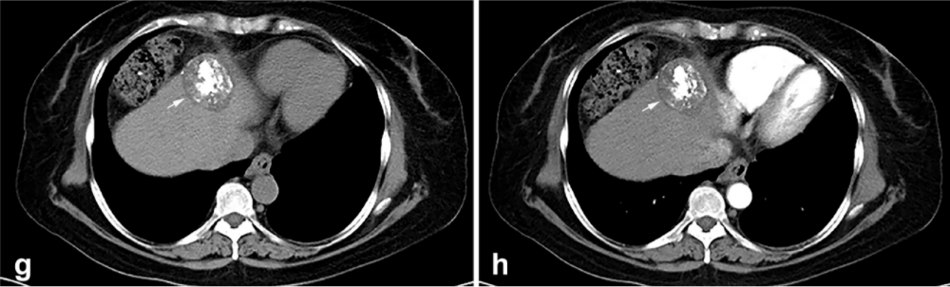

背景:由于一些原因,位于膈肌附近的腫瘤的熱消融在技術(shù)上具有挑戰(zhàn)性。首先,術(shù)中計(jì)算機(jī)掃描和超聲檢查無法清晰顯示射頻消融/微波消融切緣。第二,消融過程中不利的針分布和過熱可能導(dǎo)致肝包膜破裂,并對(duì)膈、肺和心臟造成嚴(yán)重?fù)p傷。第三,即使使用人工腹水,仍有9~22%的患者因肝周粘連或腫瘤位置靠近肝表面而導(dǎo)致膈肌熱損傷。冷凍消融可能是毗鄰膈肌的HCC的一種有前途的治療方法,因?yàn)樵谙谶^程中使用CT和US可以很好地顯示腫瘤邊緣。盡管一些研究評(píng)估了在高危區(qū)域使用冷凍消融治療HCC,但很少有研究針對(duì)膈肌臨近區(qū)域。

① 術(shù)后 1 月腫瘤治療反應(yīng):冷凍消融術(shù)后一個(gè)月腫瘤疾病控制率達(dá)95.9%。